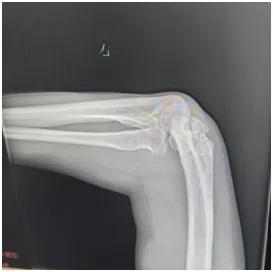

刘师傅赶忙来到郑州大学第五附属医院骨科一病区就诊。接诊医生为他安排了肘关节X线和上肢肌电图检查:

X线显示:肘关节存在明显畸形改变;

同时,刘师傅的右肘关节也出现了问题——不仅伸屈活动不灵活,外观还明显向外侧撇,正常人的肘关节本身会有一点生理性外翻(女性约10~15°,男性约5~10°左右),可医生测量后发现,刘师傅的肘关节外翻角度竟然达到了30°左右,远远超出了正常范围!